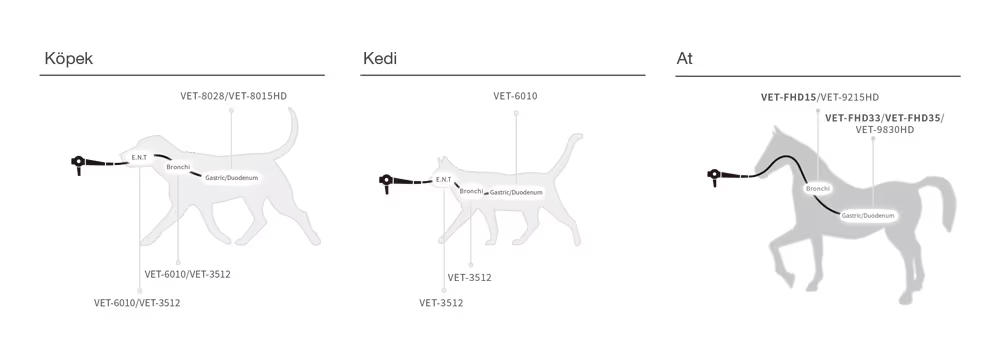

Aohua OR-100, rijit endoskop kamera sistemi, çeşitli boyutlardaki tüm rijit skoplarla uyumludur ve köpekler/kediler/egzotik hayvanlar için endoskopik tanı, artroskopik cerrahi, laparoskopik cerrahi vb. gibi hayvan endoskopik tanı ve cerrahisine olanak sağlamaktadır.